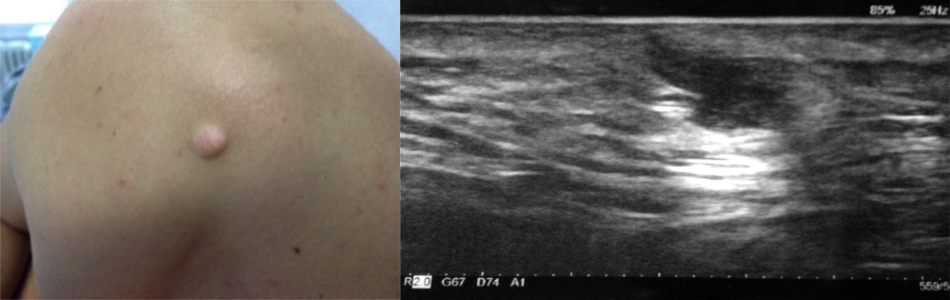

Cisti sebacea: forma a clessidra con interessamento degli strati superficiali con parete regolare, limiti ben definiti e rinforzo della parete posteriore.

Tumore benigno – pilomatricoma: lesione nodulare superficiale, mobile su piani superficiali e profondi. All’ecografia localizzata nell'epidermide e nel derma con struttura intensamente ipoecogena nel cui contesto sono presenti aree fibrocalcifiche.